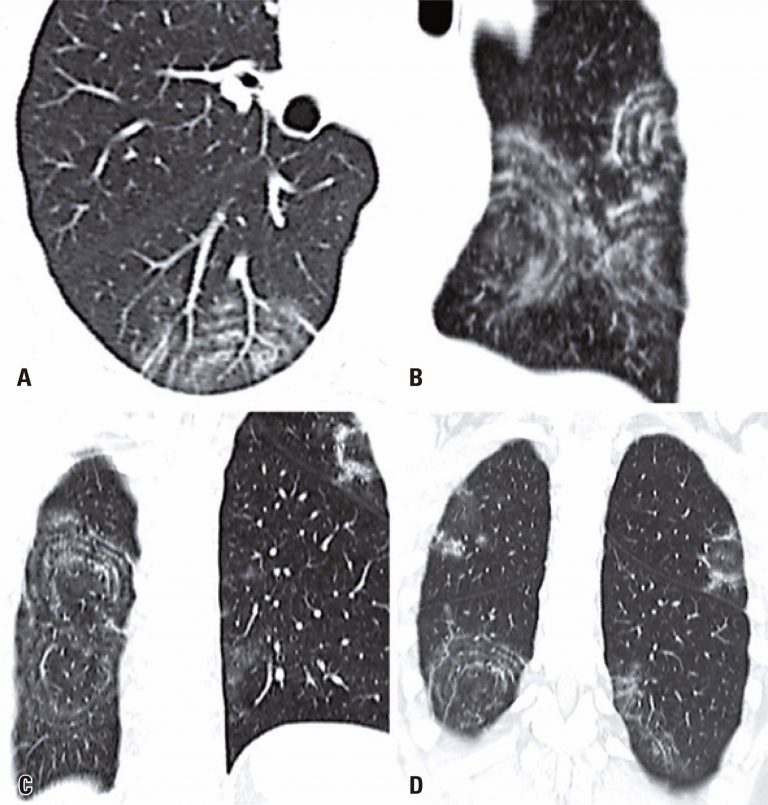

A 49-year-old man came to our emergency department with a 2-day history of fever, cough, anosmia, ageusia and odynophagia. His past medical history included hypertension. At the time of this presentation, chest computed tomography revealed peripheral and bilateral ground-glass opacities, with some visible intralobular lines – typical findings of pneumonia caused by the severe acute respiratory syndrome coronavirus 2 (SARS-CoV-2). In addition, some findings revealed the target sign (). The patient’s supportive treatment was continued, and reverse-transcriptase polymerase chain reaction (RT-PCR) confirmed the infection by SARS-CoV-2.